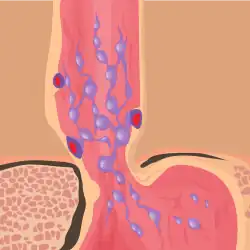

Esophageal varices are extremely dilated sub-mucosal veins in the lower third of the esophagus.[1] They are most often a consequence of portal hypertension,[2] commonly due to cirrhosis.[3] People with esophageal varices have a strong tendency to develop severe bleeding which left untreated can be fatal. Esophageal varices are typically diagnosed through an esophagogastroduodenoscopy.[4]

The upper two thirds of the esophagus are drained via the esophageal veins, which carry deoxygenated blood from the esophagus to the azygos vein, which in turn drains directly into the superior vena cava. These veins have no part in the development of esophageal varices. The lower one third of the esophagus is drained into the superficial veins lining the esophageal mucosa, which drain into the left gastric vein, which in turn drains directly into the portal vein. These superficial veins (normally only approximately 1 mm in diameter) become distended up to 1–2 cm in diameter in association with portal hypertension.

Normal portal pressure is approximately 9 mmHg compared to an inferior vena cava pressure of 2–6 mmHg. This creates a normal pressure gradient of 3–7 mmHg. If the portal pressure rises above 12 mmHg, this gradient rises to 7–10 mmHg.[5] A gradient greater than 5 mmHg is considered portal hypertension. At gradients greater than 10 mmHg, blood flowing through the hepatic portal system is redirected from the liver into areas with lower venous pressures. This means that collateral circulation develops in the lower esophagus, abdominal wall, stomach, and rectum. The small blood vessels in these areas become distended, becoming more thin-walled, and appear as varicosities.

In situations where portal pressures increase, such as with cirrhosis, there is dilation of veins in the anastomosis, leading to esophageal varices.[3] Splenic vein thrombosis is a rare condition that causes esophageal varices without a raised portal pressure. Splenectomy can cure the variceal bleeding due to splenic vein thrombosis.